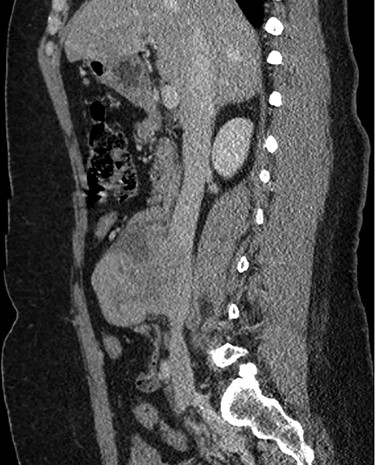

Abdominal CT scan demonstrating IVC lesion that partially encircles the aorta.

Abdominal CT demonstrating the length and location of the IVC in relation to the aorta.

Abdominal CT demonstrating the location of the tumor in the IVC.

The patient had a body mass index of 40, so combined with her presentation, age and gender. The presumptive diagnosis was of gallbladder pathology, which prompted an abdominal ultrasound. Ultrasound revealed a large 7.7 × 6.3 × 7.2 cm heterogenous, hypoechoic masslike lesion overlying the IVC (Fig 1). Abdominal CT was performed, which revealed an 8.9 × 7.9 × 9 cm multilobulated, heterogeneous soft tissue mass in the right hemiabdomen, encasing the IVC and partially encasing the distal abdominal aorta (Figs. 2–4). CT-guided biopsy was performed, which revealed an LMS.